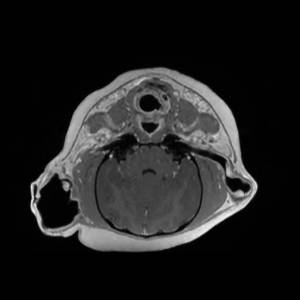

Main Gallery

Playing with a photo gallery function. It is possible to have multiple galleries, each within a namespace.